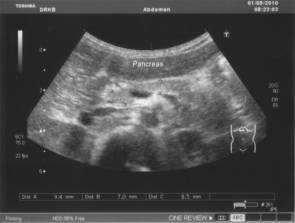

Рис. 4.5. Хронический панкреатит у ребенка 16 лет.

Гиперэхогенные включения (кисты 2×3 мм). Эхогенность паренхимы

поджелудочной железы повышена в значительной степени

Ультразвуковое исследование проводится утром, натощак.

Поджелудочная железа размеры натощак: головка 14,9 мм,

тело 16,1 мм, хвост 13,4 мм., гиперэхогенная, контуры нечеткие, гиперэхогенные

включения 2×3 мм (кисты). Диаметр селезеночной вены 4,4 мм, скорость

линейного кровотока 0,20 м/сек, объёмная скорость кровотока 0,15 л/мин.

Поджелудочная железа постпрандиально: головка 16,3 мм,

тело 13,7 мм, хвост 11,4 мм. Диаметр селезеночной вены 4,8 мм, скорость линейного кровотока 0,18 м/сек,

объёмная скорость кровотока 0,18 л/мин.

Заключение:

размеры поджелудочной железы не увеличены. Кисты размером 2×3 мм. Диаметр

СВ уменьшен, ЛСК и ОСК снижены.